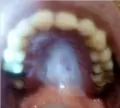

Здравствуйте. Недавно появился твердый нарост на небе. Виден как-будто белый участок немножко. На ощупь твердая шишка под слизистой. Не болит и не мешает. Что это может быть? К какому врачу можно обратиться?